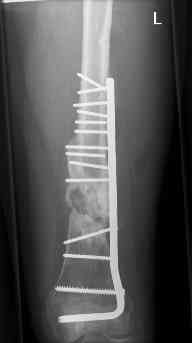

16 yr old boy, high energy motorcycle trauma trauma in July 2005 with:

- hip dislocation + acetabular fracture L

- distal femoral fracture L

- tibial shaft fracture L

- metatarsal fractures L

july 05: LISS femur, LCP plate tibia, double recon. plate post. acetabulum

oct 05: cancellous bone graft femur

aug 06: blade plate + bone graft

nov 06: revision blade plate

feb 07: retrograde nail + bone graft + BMP

may 07: dynamisation nail

sept 07: locking screw removal (max. dynamisation reached)

nov 07: persistant non-union distal femur; other fractures healed uneventfully.

All with gradual/partial weightbearing etc. Currently 50-100% weight bearing, no pain.

Soft tissues are intact. No smoking or diabetes.CRP <2